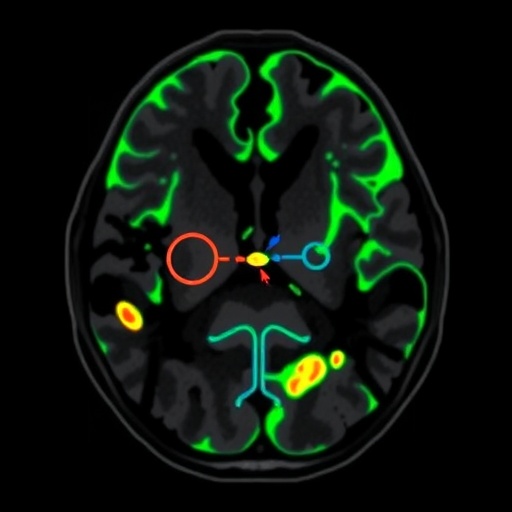

The research team utilized advanced magnetic resonance imaging techniques to identify specific biomarkers associated with GPC3 expression. By correlating the imaging characteristics with histopathological features, the study delineates a pathway where MRI can serve as a non-invasive method to infer not just the presence of tumors, but their underlying biological behavior. This innovative approach could significantly alleviate the need for invasive biopsies, minimizing patient discomfort and risk.

In this study, the authors employed radiogenomics, integrating genomic data with radiological imaging, to unravel how imaging phenotypes can reflect molecular alterations in the tumor microenvironment. This innovative methodology represents a paradigm shift in how oncologists approach diagnosis and treatment for HCC, taking into account both the structural and functional aspects of tumors. The precision obtained through such an approach indicates that personalized medicine could be more achievable in oncology than previously thought.

The researchers meticulously analyzed MRI data from a cohort of HCC patients, employing machine learning algorithms to enhance the predictive power of the identified radiogenomic biomarkers. They found that specific imaging features were significantly associated with high GPC3 expression. These findings suggest that artificial intelligence can be a valuable ally in oncology, driving forward the frontier of predictive medicine and offering enhanced decision-making tools for clinicians.